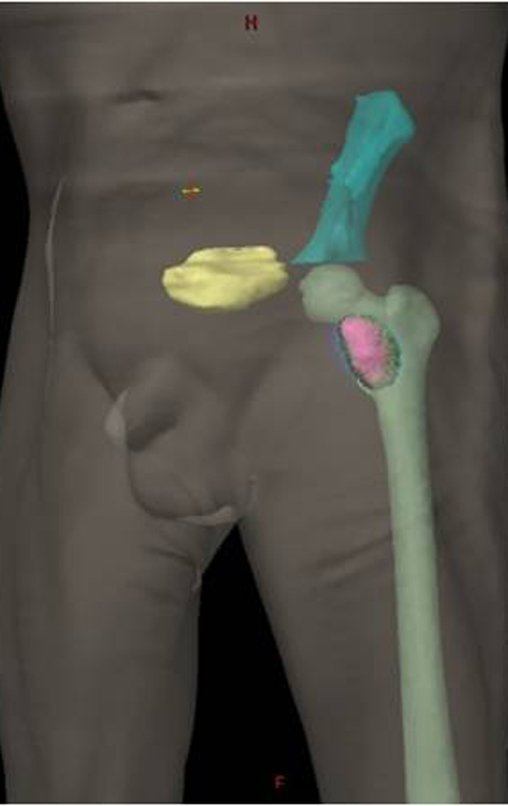

Técnica de Ressecção de Metástase Óssea de Tumor Renal no Fêmur. Paciente masculino, com 57 anos de idade, refere aparecimento de lombalgia, em final de outubro de 2014, com irradiação para o MIE. Devido a progressão dos sintomas, realizou uma ressonância da coluna que relatou presença de hérnia discal L5-S1. Iniciou fisioterapia e com a piora dos sintomas realizou uma tomografia em 18/02/2015, com relato de artrose facetaria L2-L3, L3-L4 e discopatia L5-S1 com protrusão ao canal medular e radiografias da bacia, figuras 1 e 2.

No dia seguinte, em 19/02/2015, fez ressonância, agora do quadril, onde aparece lesão osteolítica no colo femoral esquerdo e região do trocânter menor, de 3,6 cm de diâmetro, com componente de tecidos moles infiltrando tendões e músculos, figuras 3 a 9.

Repetiu a radiografia e realizou tomografia em 20/02/2015, figuras 10 a 13.